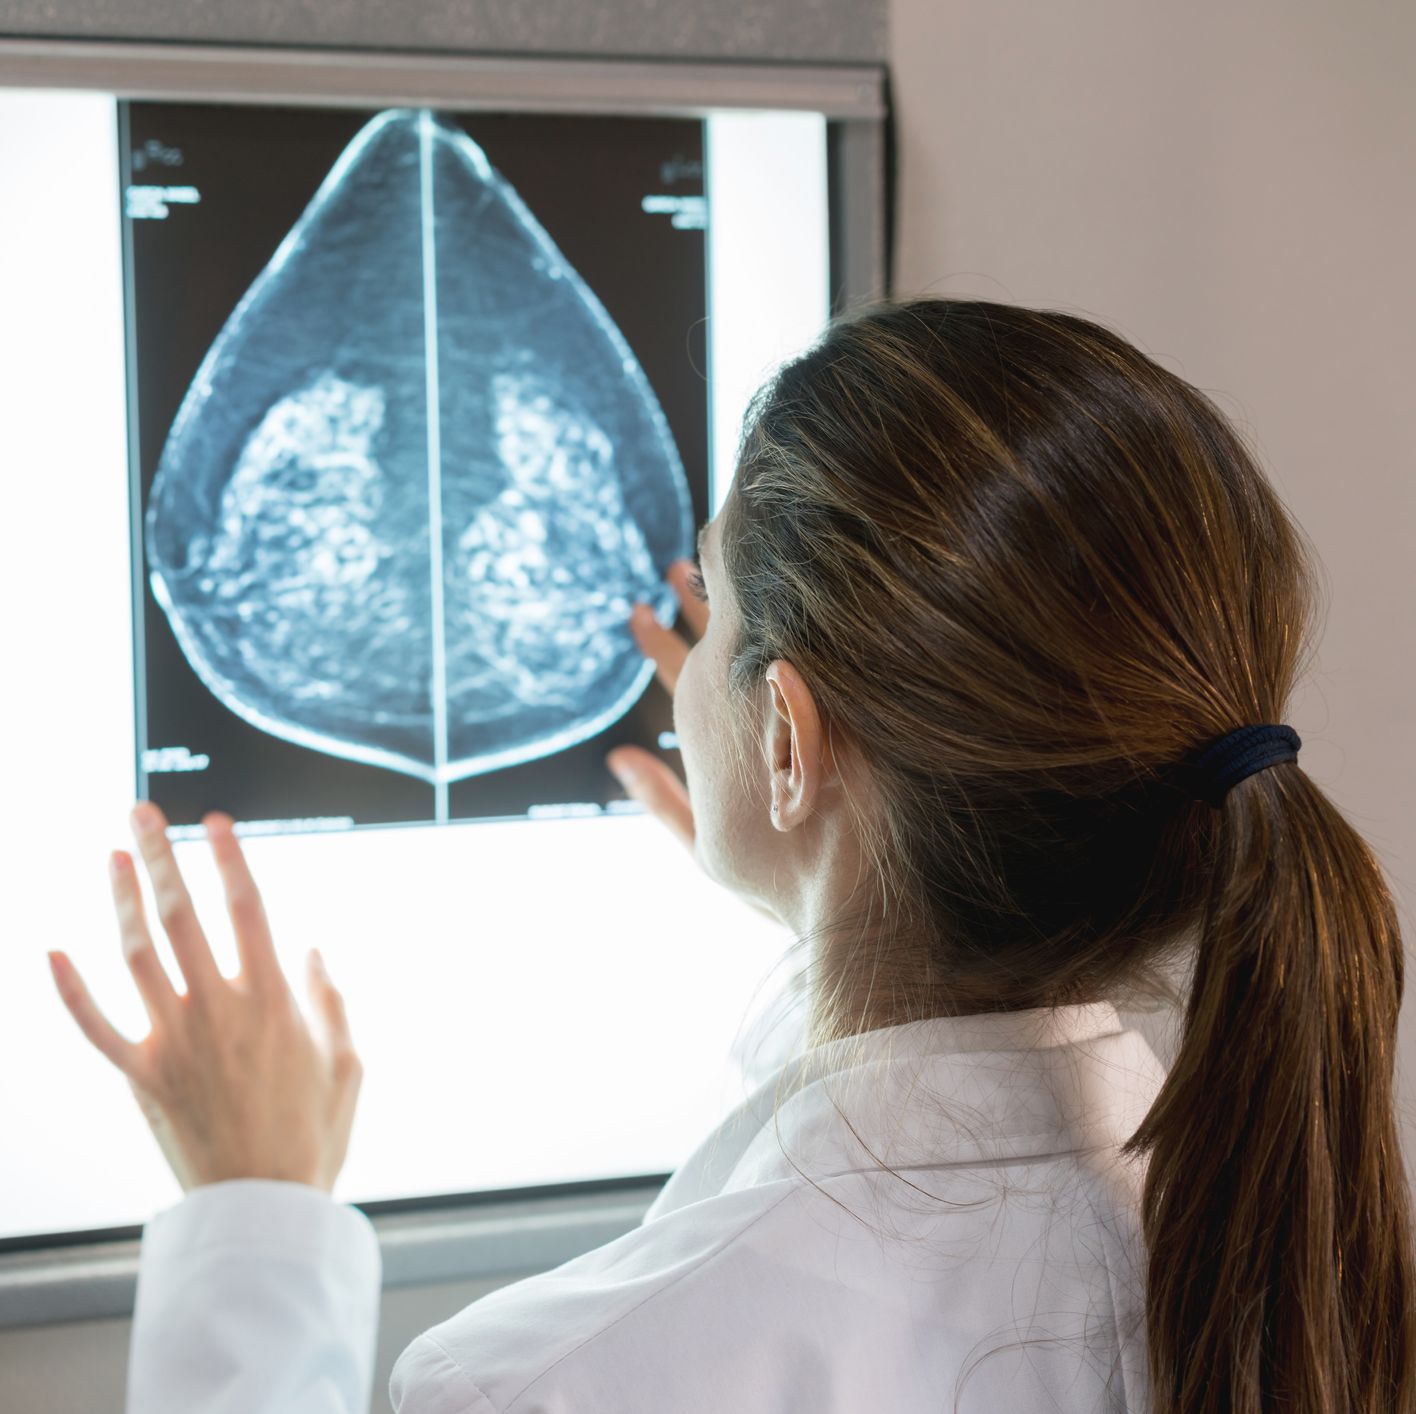

Anuncio - Continúe leyendo a continuaciónEs necesario hacer mamografías regulares. andresr Getty Images

andresr Getty Images"La recomendación actual es que todas las mujeres de 40 años o más se hagan una mamografía anual", dice el Dr. Bank. Señala que las mamografías están cubiertas por el seguro y que hay muchas organizaciones que ofrecen mamografías gratuitas para las mujeres que no tienen seguro, por lo que no debe dejar que sus temores financieros se interpongan en el camino de una prueba que puede salvar su vida. "Las mamografías regulares son las mejores pruebas que tienen los médicos para detectar el cáncer de mama a tiempo", dice la Dra. Dorraya El-Ashry, directora científica de la Fundación de Investigación del Cáncer de Mama. Puede que hayas oído que la mamografía no detecta todos los tipos de cáncer de mama, especialmente si tienes los pechos densos, y pienses: "¿Qué sentido tiene? Sin embargo, una mamografía es el primer paso en la detección y puede señalar si usted podría beneficiarse de un ultrasonido de todo el seno o de una resonancia magnética (MRI), que pueden detectar tumores en senos densos. "En los últimos diez años ha habido una tremenda mejora y sigue habiendo mejoras en el perfeccionamiento de la tecnología de imágenes y en su precisión", dice El-Ashry. De hecho, ahora mismo la BCRF está financiando la investigación sobre la mamografía espectral con contraste mejorado (CESM) para ver si puede proporcionar una exploración aún más precisa para las mujeres con senos densos.